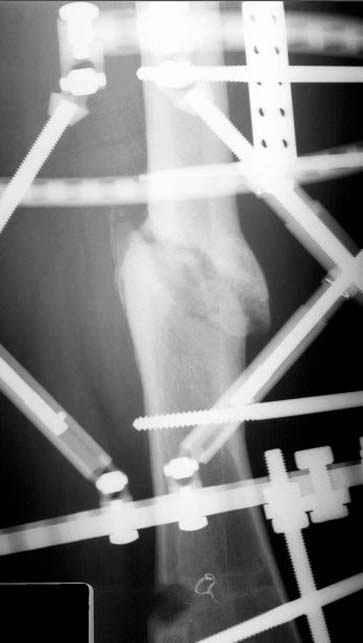

пластическая модель; и коррекция бедра аппаратом Илизарова.

Почему не замена гвоздя с рассверливанием, а аппарат?

Отправитель: Alexander Chelnokov 23 Ноябрь 2004, 21:29

хотя даже если бы и инфекция , то nail exchange с рассверливанием канала - вариант дебрайдмента) Я думаю, что последовательность развития событий:

Узкий к-м канал - тонкий гвоздь- усталостный перелом дистальных винтов - развитие нестабильности и как ее результат остеолиз вокруг гвоздя - деформация анатомической оси бедра. Похоже, что я понял почему аппарат, а не новый гвоздь:-)

ЕТ - Изначально костно-мозговой канал бедра был узкий, дальнейшее его рассверливание ещё больше скомпрометирует прочность бедра( латеральный кортекс дистального отломка уже истончен), приведет к дефекту наружной стенки - хотя это только мои догадки - хотелось бы знать мнение Джолдаса о выбранной тактике.